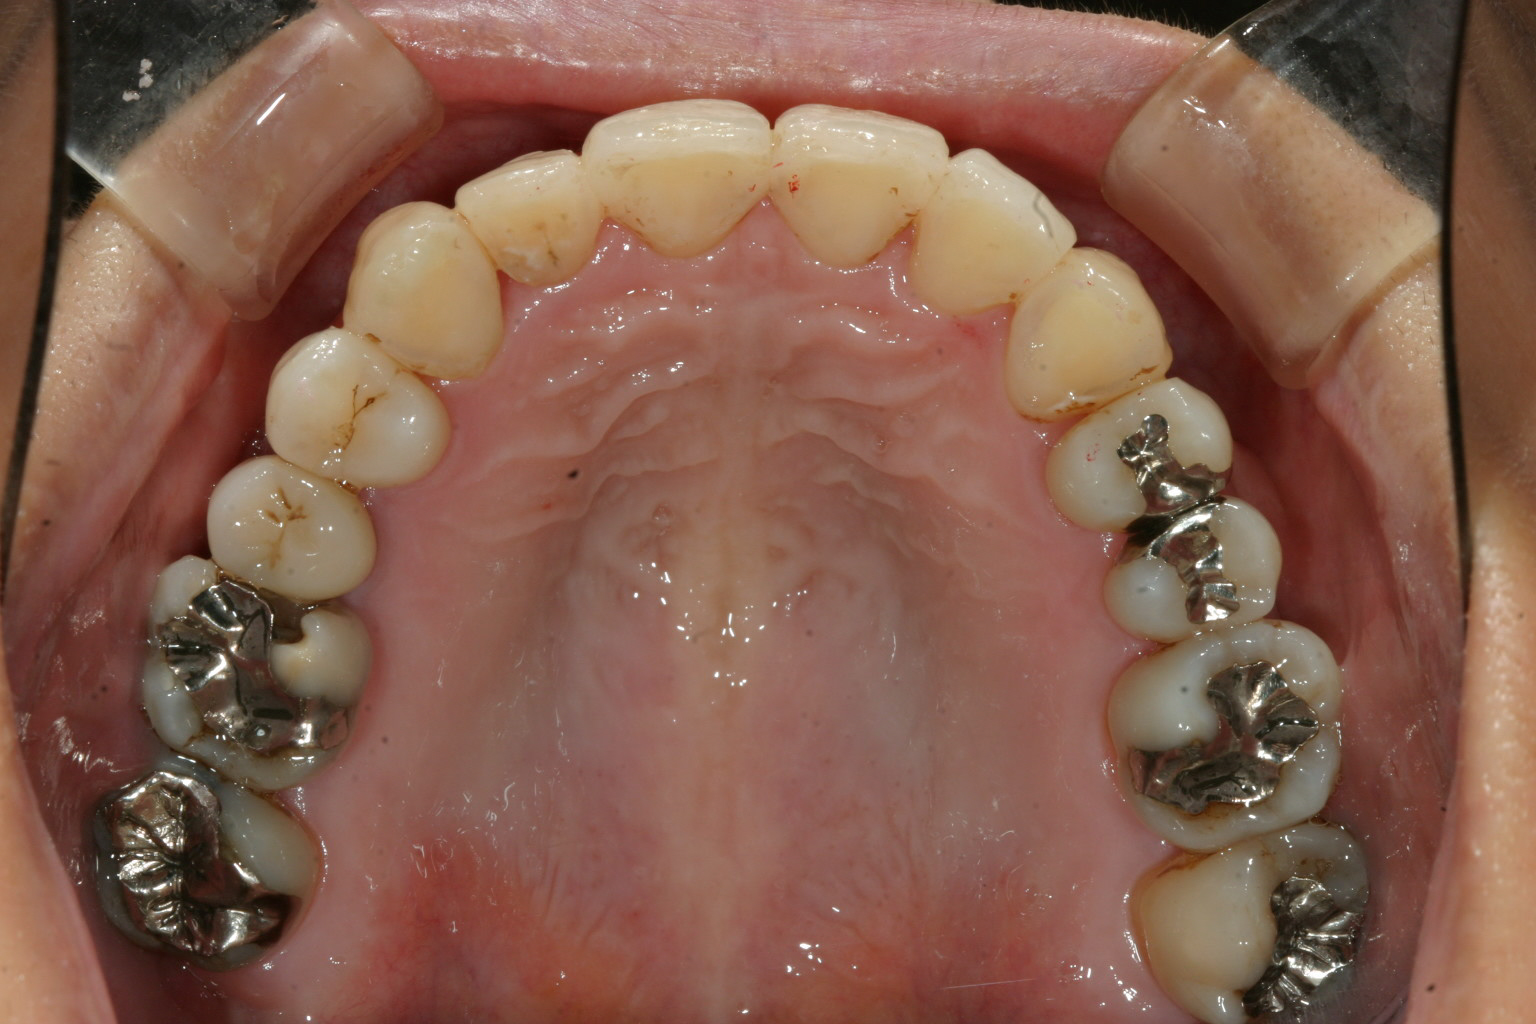

かなり酷くガタガタになってますね~ 数本の回転してる歯が在りますね~